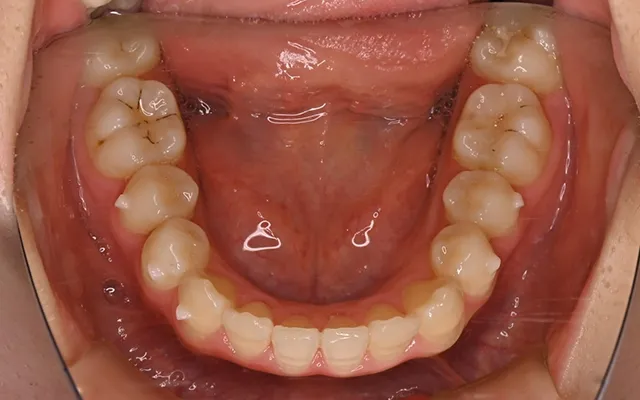

- AFTER

-

| 治療内容 | インビザラインGOによる矯正治療 |

| 費用 | 429,000円 |

| 期間 | 4か月 |